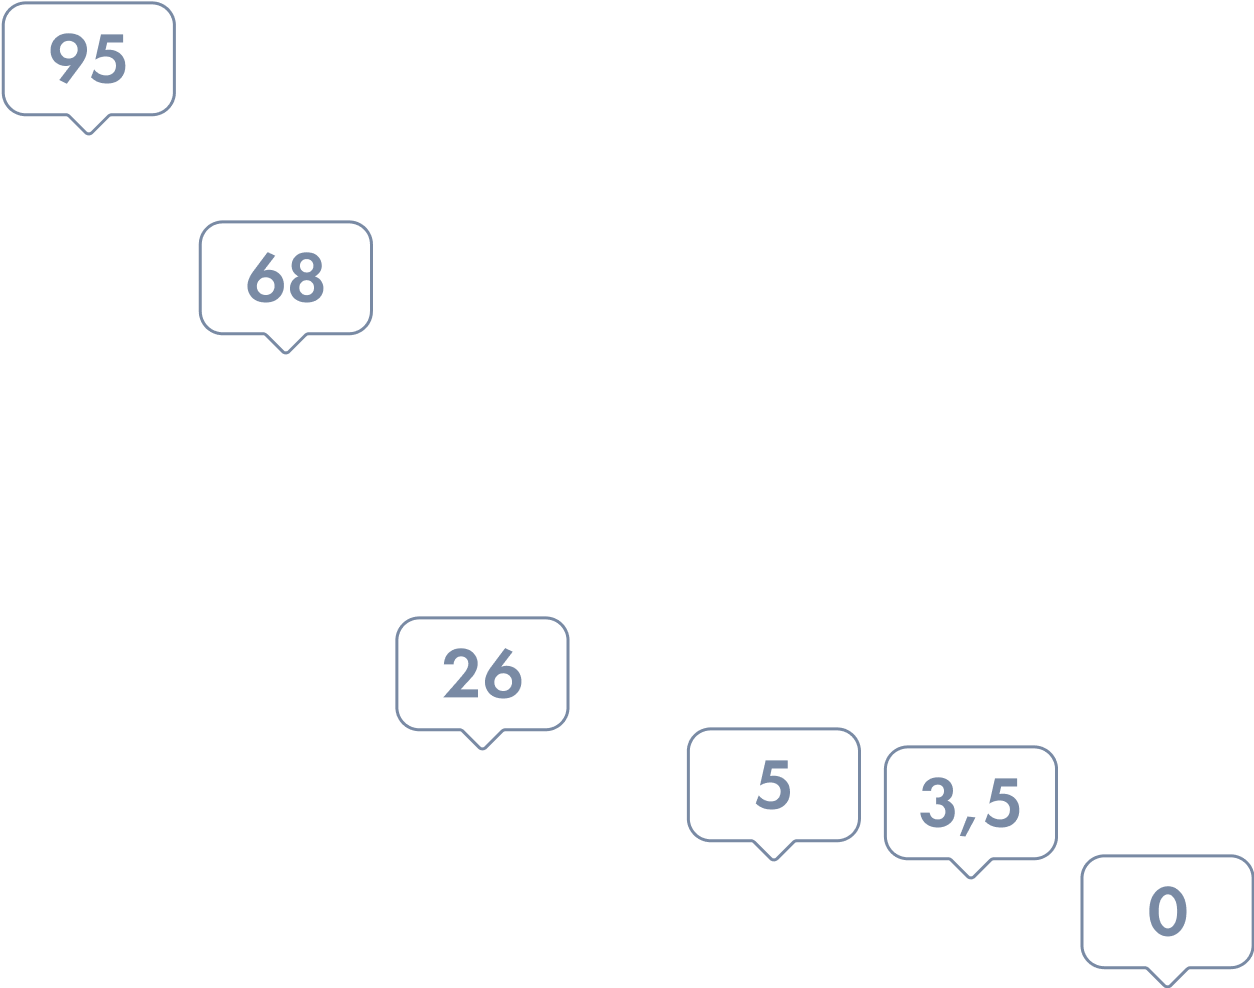

- Пушкарь Д. Ю., Берников А. Н., Раснер П. И., Бормотин А. В., Дьяков В. В., Шведов А. М. Фуразидин (Фурамаг®) в лечении острого и рецидивирующего цистита у женщин. Вестник урологии. 2024;12(6): 83-88. DOI: 10.21886/2308-6424-2024-12-6-83-88.